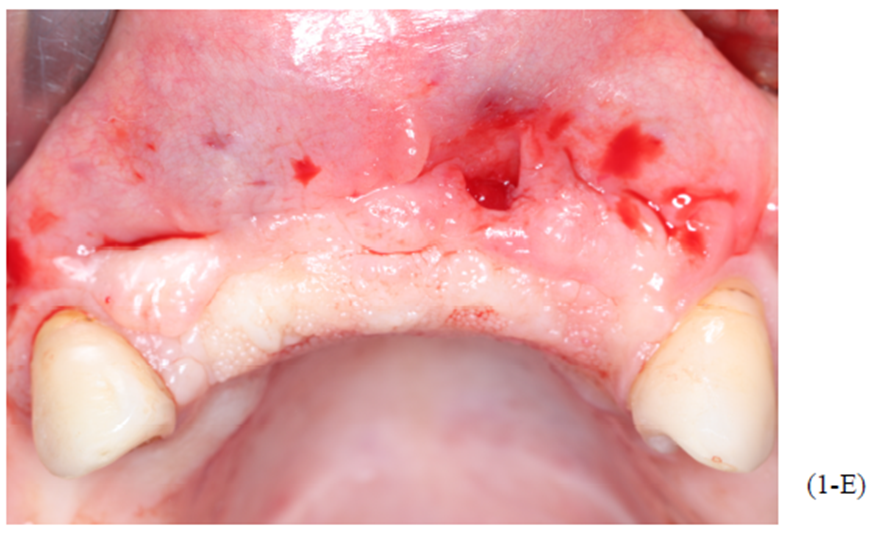

Figuras A,B,C, D e E: imagens evidenciando grande perda óssea anterior no sentido horizontal, bem como a vestibularização do rebordo anterior, o que impossibilita a instalação dos implantes em um bom posicionamento tridimensional.

Foram planejados quatro implantes do tipo Cone Morse Maestro Implacil De Bortoli 3.5 x 11 mm. Após remoção de maneira facilitada dos parafusos tenda, foram instalados quatro implantes em ótimo posicionamento tridimensional como evidencia as Figuras 1-E, 1-F, 1-G e 1-H). Todos apresentaram estabilidade primária de 35 Ncm de torque, e aguardamos quatro meses para posterior reabilitação protética definitiva com próteses metalocerâmicas individualizadas do tipo parafusada.